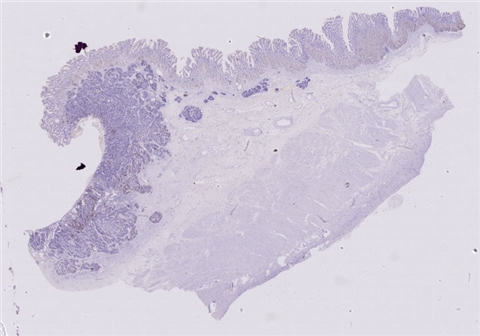

患者详情: 患者于半年前无明显诱因出现大便带血,为暗红色血便,未见粘液脓血便,反复发作,无腹痛腹胀,伴大便次数增多,并大便不成形,逐渐变细,初未引起重视,亦未行相应治疗,后症状逐渐加重。为进一步诊治,2020年3月入住我院。 直肠指诊:括约肌紧张度:正常,狭窄:无,触痛:无,距离肛门口大约4cm可及一环直肠一周肿块,质硬,移动度差,无压痛,指尖稍可通过肿块,指套染血:有。 电子肠镜示:距肛门4cm直肠处可见一巨大新生物,中间凹陷,底覆污秽苔,环2/3腔生长,钳取6块送病理,余 结肠各段粘膜光整,血管纹理清晰,未见明显的溃疡、息肉。 活检病理示:恶性肿瘤。后行腹腔镜直肠癌根治术。

大体所见: 1、直肠癌肿物:已切开肠管一段,长10cm,一侧切缘周长4cm,另一侧切缘已缝合,长3cm,紧邻缝合切缘见一溃疡型肿物,大小4.5*4*3cm,肿物切面灰白灰黄色、质硬,与周围组织分界欠清,侵及全层。

2、上切缘:灰褐色黏膜组织一块,大小1*1*0.4cm。

3、下切缘:灰褐色黏膜组织一块,大小1.2*1*0.4cm。

免疫组化: 2002032-004#:CgA(弱+)、syn(+)、CD56(+)、 2002032-002#:CK(+)、TTF-1(+)、CD34 +、SMA(-)

医院: 赣南医学院第一附属医院